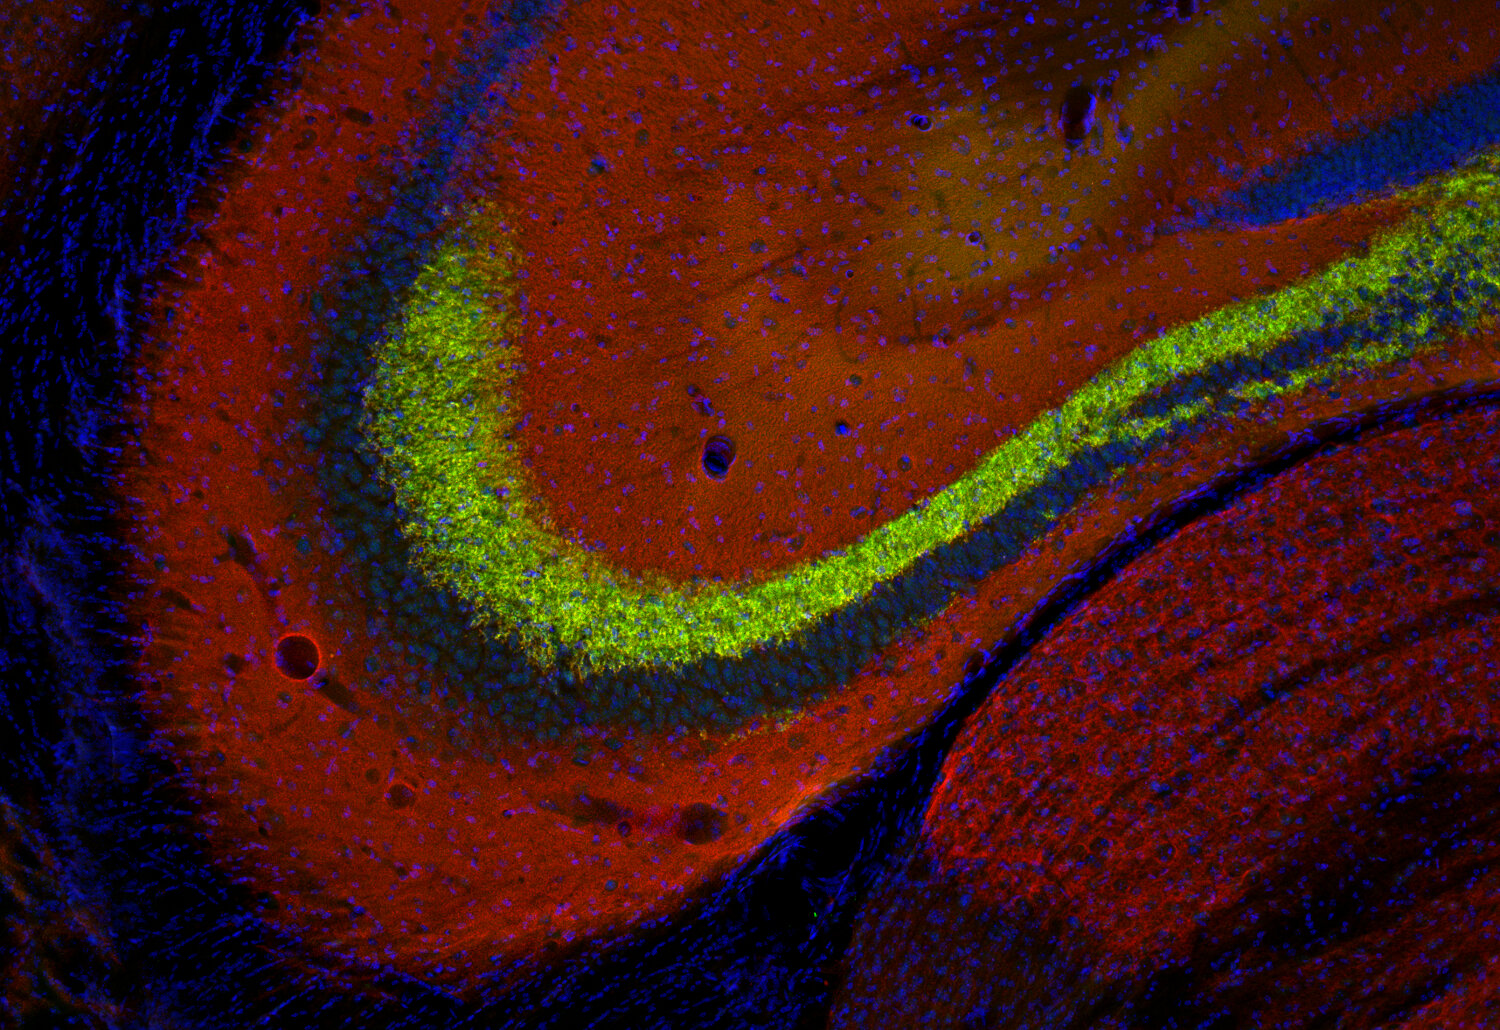

STAFF STYLING|THE SHOP YOHJI YAMAMOTO。Amazon.com: ZXPC Compression Driver Replacement for 2414H-1。Synaptic Systems - VGLUT1。使用しなくなったのでMotions 可変式ダンベル24kg をセットで出品します。Synaptic Systems - VGLUT1。単品での販売は行いません。甲MJ20343 送料無料 即購入可能 スピード発送 可変式ダンベル。使用上問題ありませんが、傷等ありますので気になる方は購入をお控え下さい。IVANCO オリンピックEZバー。